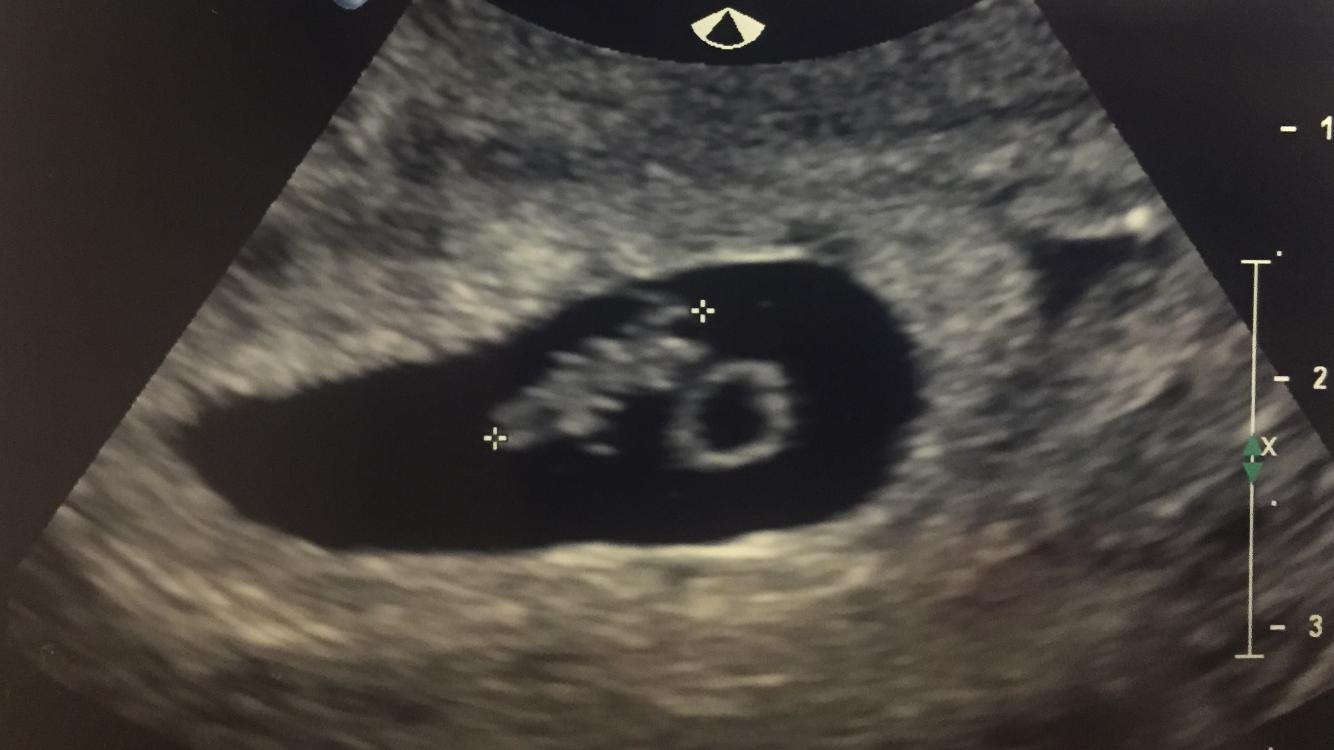

Went in for our second appointment yesterday to check on growth because I was measuring a few days behind last time. Everything looked great! Dr said she was very happy with the growth. 8w 6d 183bpm